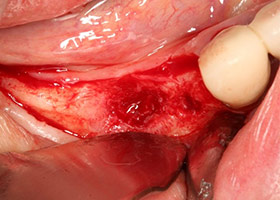

2.病患右下排,治療前狀況。

3.照片顯示此區域牙周破壞嚴重。

4.移除牙橋與殘根,牙脊明顯萎縮。